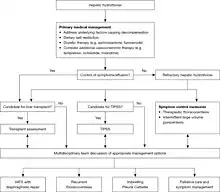

Management

As the condition is caused by leaking ascitic fluid, treatment centers around managing ascites and decompensated liver disease. Some individuals respond to medical management. In up to 26% of cases, the condition does not respond to medical management, in which case it is known as a refractory hepatic hydrothorax. For these individuals, the first treatment of choice is the insertion of a transjugular intrahepatic portosystemic shunt. The only curative treatment is a liver transplant. Additionally, treatment involves addressing the underlying cause of the liver disease, such as alcohol use or viral hepatitis.[6]

Refractory hepatic hydrothorax

For people with refractory hepatic hydrothorax, the only definite treatment is a liver transplant. However, the majority of people with this condition are unsuitable for transplantation, and the majority of those who have died awaiting it. However, other treatments can improve symptoms, increase survival, and, ideally, give time until a liver transplant is available.[4] Suitability for liver transplantation is determined by the UKELD score; a score >49 indicates need for transplant listing. Additional indicators include empyema development and a failing synthetic liver.[1]

Transjugular intrahepatic portosystemic shunt

The main treatment in those with refractory hepatic hydrothorax is the insertion of a transjugular intrahepatic portosystemic shunt (TIPS). TIPS decompresses the portal system, reducing portal venous pressure and fluid in the abdomen; it is estimated to work in 70-80% of cases. However, it does not improve the prognosis in those with end-stage liver disease.[8] In people with serious liver dysfunction, TIPS may cause liver failure, as it shunts blood away from the liver.